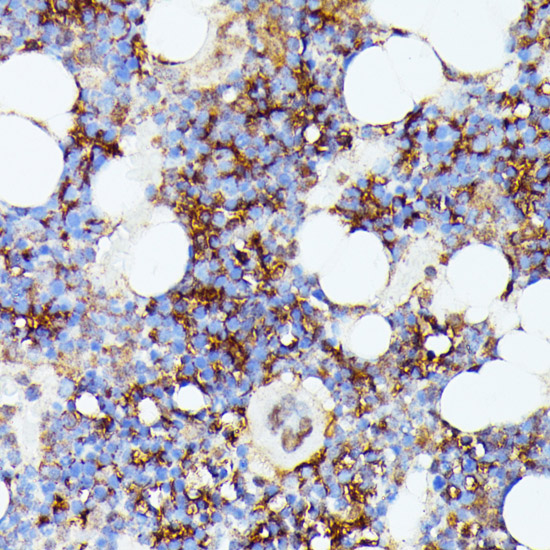

DescriptionIba1 Polyclonal Antibody. Unconjugated. Raised in: Rabbit.

ImmunogenRecombinant fusion protein containing a sequence corresponding to amino acids 1-147 of human Iba1 (NP_001614.3).

ApplicationWB, IHC, IF; Recommended dilution: WB 1:500 - 1:2000, IHC 1:50 - 1:100, IF 1:50 - 1:100